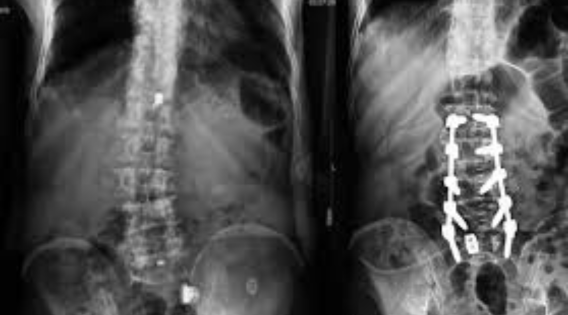

Minimal Access and Minimally Invasive Surgery of the Spine

By drastically reducing the surgical trauma, recovery time, and long-term positive effects of the operation, minimally invasive spine surgery (MISS) has revolutionized spine care. Current patients want doctors who are experts and proficient in such operations as:

Consequently, there has been an increased demand for the best Minimal Access Spine Surgeon India. This demand is mostly due to those patients who require less tissue damage, quicker recovery, and shorter hospitalization. Several top spine neurosurgeons in Kolkata have embraced these cutting-edge methods, thus enabling their patients to successfully achieve the needed safety and precision balance.